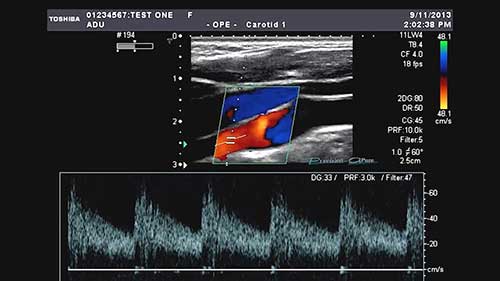

M型超声

简介:M型超声的M代表“运动”(Motion),这是一种更早期的成像模式,但时至今日仍常被用来分析结构的运动。